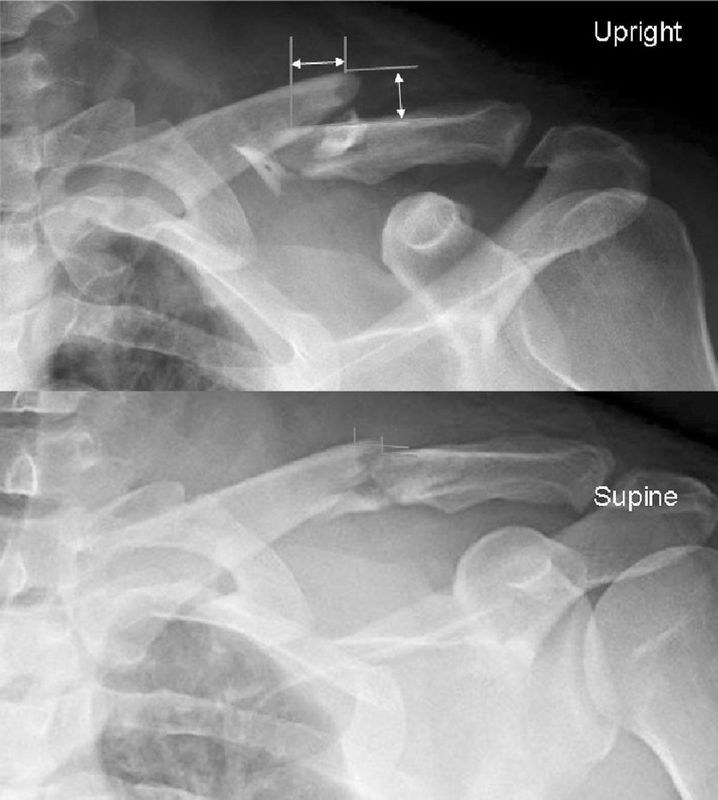

锁骨远端骨折

胡新锋医生的科普号

2023年03月30日